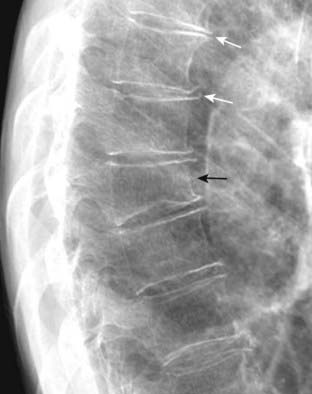

Figure 2-8 Osteoporotic compression fracture and degenerative disk disease.

Don’t forget to look at the thoracic spine when studying the lateral chest radiograph for valuable information about a host of systemic diseases (see Chapter 24). In this study, loss of stature of the 8th thoracic vertebral body is due to osteoporosis (solid black arrow). Compression fractures frequently involve the superior endplate first. Small osteophytes are present at multiple levels from degenerative disk disease (solid white arrows).